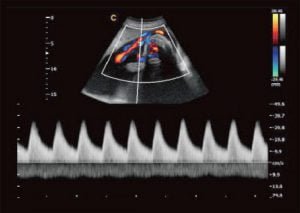

Imágenes Cardiológicas